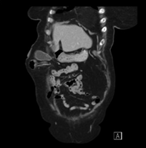

Endovascular intervention for iliac vein thrombosis after simultaneous kidney-pancreas transplant

Meredith Gunder and others

Journal of Surgical Case Reports, Volume 2019, Issue 4, April 2019, rjz024, https://doi.org/10.1093/jscr/rjz024